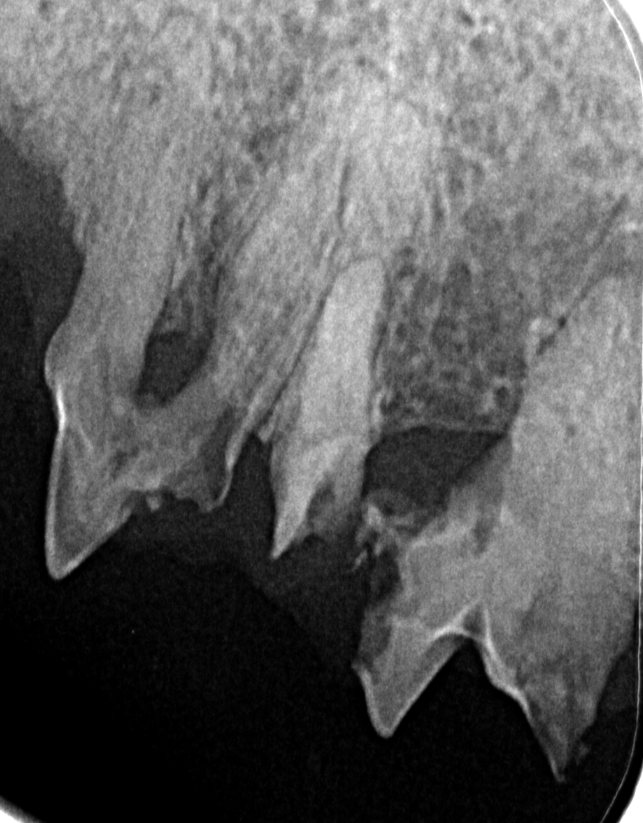

Photo 3 - abgebauter Knochen

Photo 5 - abgebauter KnochenPhoto 4 - abgebauter Knochen

Auf den 3 Bildern sieht man jeweils wie der Knochen sich aufgrund einer Entzündung abgebaut hat.

Werden die Zähne geröntgt, können wir sehen was genau mit dem Knochen durch die Entzündung passiert ist und welcher Zahn gezogen werden muss. Ohne Röntgen sieht man nur die Spitze des Eisberges.